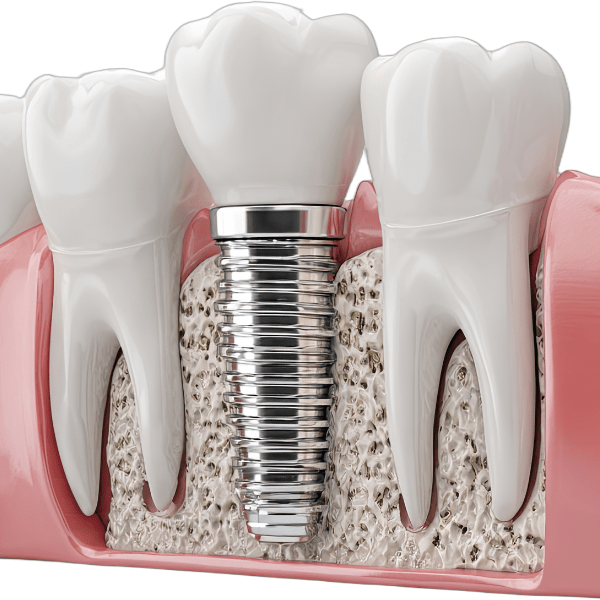

Instead of waiting weeks or months for healing before implant placement, both steps are completed in a single visit. This technique helps preserve jawbone structure, maintain healthy gum contours, and significantly shorten the overall treatment time- making Summirow a preferred choice for the Best Immediate Dental Implants in Surat.

Immediate placement helps reduce bone shrinkage that typically follows tooth extraction.

From gentle extractions to smooth implant placement, your comfort is prioritized at every stage.